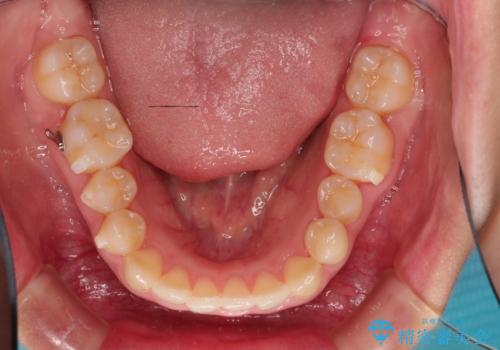

初診時の歯並びの状態としては、上下とも前歯部の中等度のがたつきがあり、その他に奥歯の噛み合わせのズレや、口元の突出感も認められました。

奥歯の嚙み合わせのズレを改善するにあたり、カリエールディスタライザーという装置を併用することで治療期間の短縮を図りました。

本症例は、見た目、嚙み合わせ及び、治療期間や施術内容にご満足いただきました。